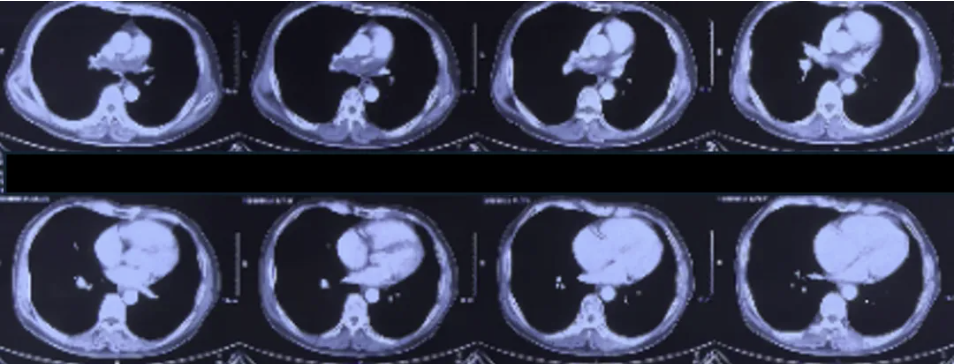

遂就诊于心内科,CTPA(如下图):肺动脉主干及分支栓塞;下肢静脉超声:左侧髂外静脉不完全血栓形成;右侧肌间静脉血流瘀滞。予低分子肝素抗凝治疗,10月23日出院,予利伐沙班15mg bid治疗,11月5日减量为10mg bid。